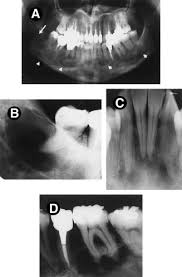

Difficulties In The Diagnosis Of Periapical Translucencies And In The Classification Of Cemento Osseous Dysplasia Bmc Oral Health Full Text

Difficulties In The Diagnosis Of Periapical Translucencies And In The Classification Of Cemento Osseous Dysplasia Bmc Oral Health Full Text from media.springernature.com